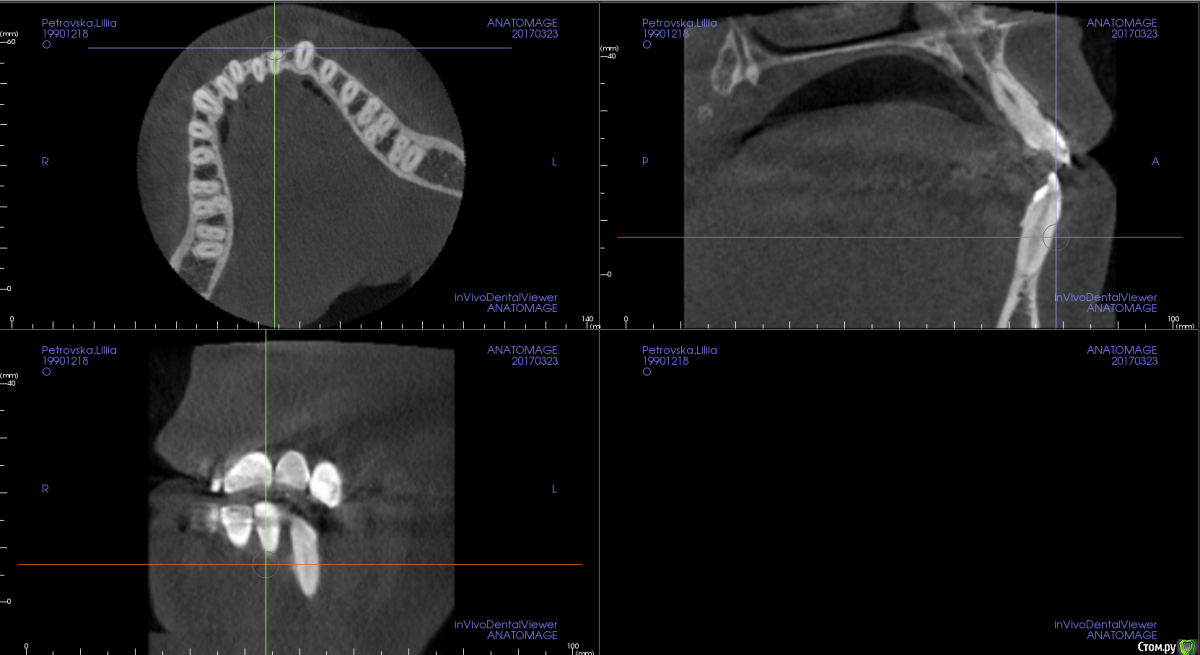

Opdihatop Опубликовано 4 марта, 2017 Поделиться Опубликовано 4 марта, 2017 И снова здравствуйте, коллеги. Вот такой вот случай к рассмотрению. Много лет назад пациентка уже проходила "камуфляжное" лечение. Со слов пациентки оно было закончено с передним открытым прикусом. Сейчас ситуация такая. Пациентка думает над ортохирургией, но меня смущает фронт н/ч. И по снимкам и по ситуации во рту корни 32, 31, 42, 43 зубов фенестрировали лингвальную кортикалку почти на всем протяжении, 33 - вестибулярную. Вопрос вот в чем: что делатьс этими зубами? Возможно ли их поставить на место? Или лучше не трогать, дольше простоят? Ссылка на комментарий

m.d.n Опубликовано 20 марта, 2017 Поделиться Опубликовано 20 марта, 2017 срезы кт покажите . на чем остановились Ссылка на комментарий

Opdihatop Опубликовано 26 марта, 2017 Автор Поделиться Опубликовано 26 марта, 2017 Прошу:313233414243 Ссылка на комментарий